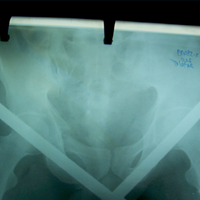

Case:8 Polytrauma

Patient having closed segmented fracture midshaft & lower 1/3 Tibia with closed fracture superior & inferior pubic rami right side with pelvis fracture following vehicular accident wastreated with intramedullary nail for fracture tibia and external fixator for fracture pelvis.

Pre-Op

Immdiate Post-op

Ex fix with frame